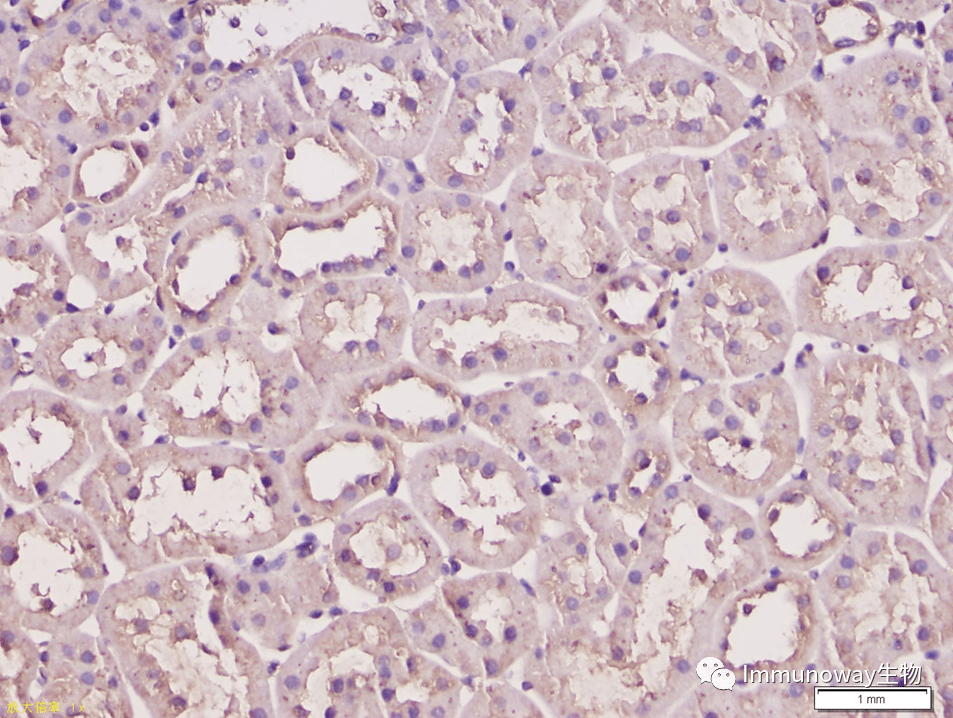

免疫组化(ihc-p)